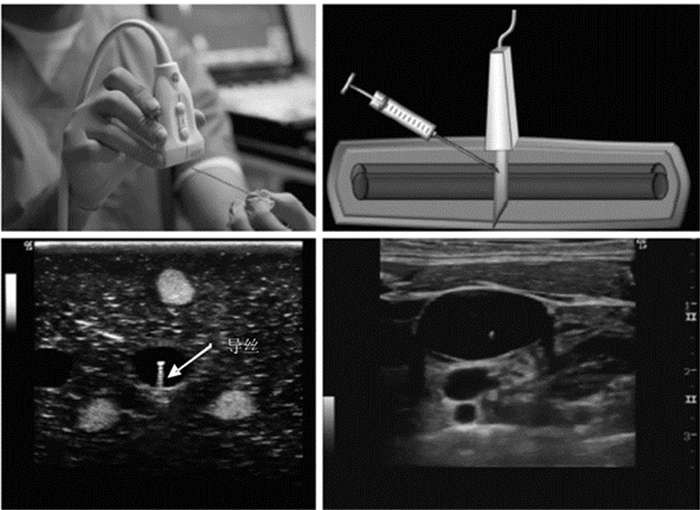

3.6 床旁超声在介入操作中的临床应用 3.6.1 概述

动静脉穿刺置管和浆膜腔穿刺是危重症治疗的常见技术。超声能够清晰地显示人体深部组织结构,并能对目标进行准确定位,同时还能实时观察目标的动态变化,避免严重并发症[41, 42, 43, 44],这使得超声引导穿刺技术应运而生。目前超声引导下穿刺技术已经广泛运用于临床,成为各种临床有创操作的安全保障。

3.6.2 介入操作的超声应用步骤及方法床旁超声引导下的介入操作基本原则包括:穿刺前常规进行超声检查,设计穿刺路径、测量穿刺深度等;选择合适的进针途径和最佳穿刺点,有效避免并发症。超声引导下穿刺,应选择评估合适的进针位置、深度;穿刺时超声引导,应降低显示深度,将穿刺针及针尖显示在屏幕上。

(1)超声引导血管穿刺 穿刺前首先应该在超声下识别目标血管,超声引导下血管穿刺有平面内(纵断面)和平面外(横断面)两种方法,它们各有特点,在实际操作中应该综合利用,互相补充。

平面内穿刺法(纵断面法)(图 40):是指超声探头长轴、血管长轴、穿刺针均位于同一平面内的超声引导穿刺方法。此种方法最大的优点是整个穿刺过程中穿刺针的全长及行进途径均始终显示在超声影像中,非常直观,全程可见,并发症少;其缺点主要是穿刺过程中容易丢失目标血管而误穿伴行的其他血管。

|

平面外穿刺法(横断面法)(图 41):是指超声探头长轴与血管长轴及穿刺针垂直的穿刺方法。此种方法穿刺针行;容易从血管壁正中穿入血管,减少血管侧壁损伤可能;穿刺过程中能始终监测伴行血管情况,避免误穿。其缺点是穿刺过程中仅能看见穿刺针的针尖(超声影像上表现为一后方伴有明显混响伪影的高回声亮点),无法看见穿刺针全程;针尖位置不易被识别,容易造成穿刺过深,穿透血管甚至损伤深层组织器。

|

| 图 41 平面外穿刺法 |

超声探头多选择腹部探头。超声定位并标记腹腔穿刺点,一般选择“反麦氏点”或腹水最深处,且避开腹内脏器、如漂浮的肠管、膀胱、肝脾等。整个操作过程中都在超声引导下进行。针尖及导丝一旦进入无回声的液体区时就可表现为强回声影(图 44)。

|

| 图 44 腹水中漂浮的肠袢(左上),箭头所示;穿刺针尖(右上);置入导丝(左下);置入导管(右下) |